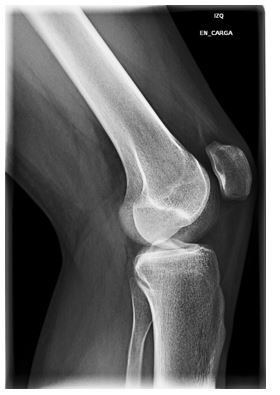

Imagen de rodilla izquierda para evaluar posible artrosis de rodilla, patología musculoesquelética altamemente prevalente. Fuente: UPM